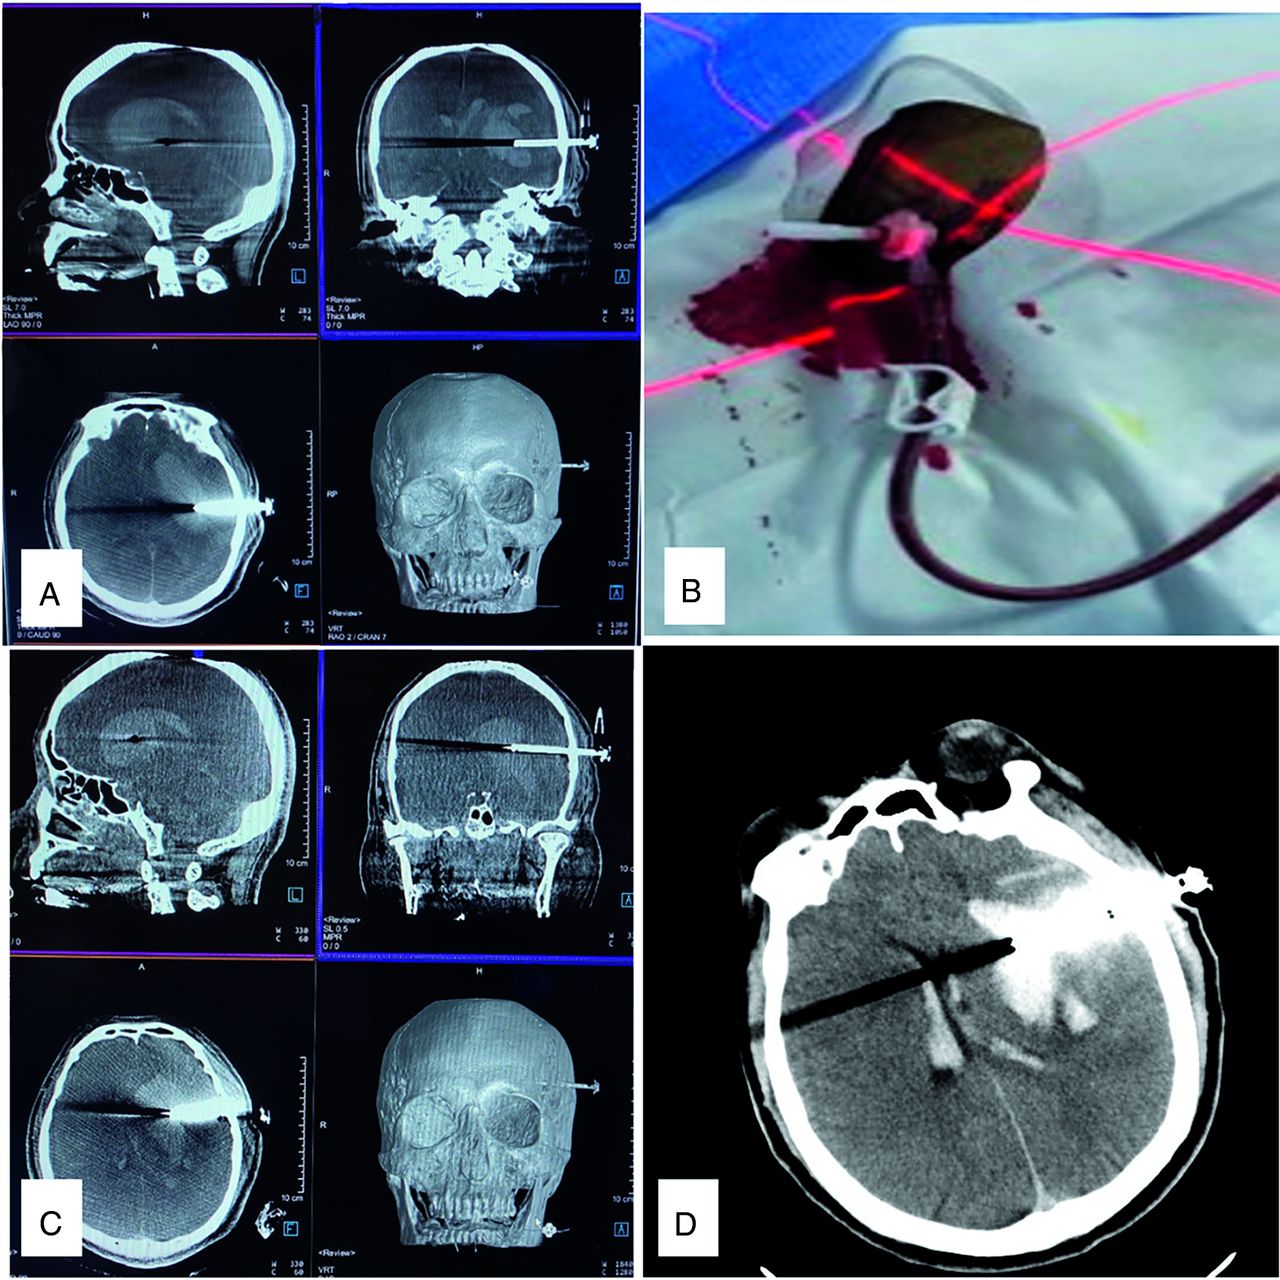

For patients with a large hematoma volume, it is often difficult to achieve a satisfactory hematoma-removal effect with 1 puncture aspiration. FDCT in the operation enables the surgeon to monitor the situation in real-time and perform a second puncture under sterile conditions if necessary (Fig 2). Aspiration was stopped when the hematoma volume was reduced by two-thirds or was <15 mL, shown in the FDCT image.

Monitoring of intraoperative hematoma evacuation under FDCT. The patient had an estimated hematoma volume of 45 mL. A, Discharge of 10 mL from the first hematoma. B, Laser crosshair indicated the second puncture entry point. C, A second puncture was performed, and the needle position was confirmed under FDCT. A total estimated volume of 25 mL of hematoma was aspirated. D, Postoperative CT shows a residual hematoma of 10 mL.